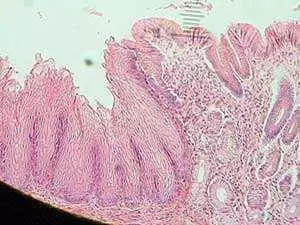

For their study, they reviewed histopathology reports of esophageal biopsies to identify all cases of increased esophageal eosinophilia.

The team defined cases of eosinophilic esophagitis as those where biopsies showed Z15 eosinophils per high power field and, which also included associated symptoms.